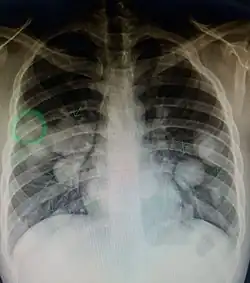

Metastatic cancer in the lungs -